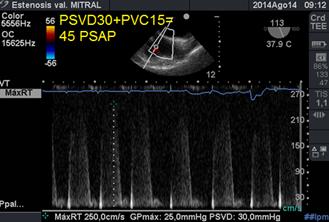

La disfunción ventricular derecha (VD), puede estar presente y puede indicar mal pronóstico, es importante en el examen ecocardiográfico(37) inicial, documentar no sólo el grado de hipertensión pulmonar sino también la función sistólica del VD (a través de TAPSE y s´tisular).(38) (39) La medición de la presión sistólica de la arteria pulmonar (PSAP) se realiza a través de la medición de la presión sistólica del VD medida con Doppler Continuo, en el reflujo tricuspídeo (desde la vista ecocardiográfica bicava modificada entre 50° y 70°)(Figura 23); a lo que sumamos la presión de aurícula, presión venosa central (PVC): (40)(41)

Figura 23 imagen bicava modificada: medición de la presión sistólica de arteria pulmonarcon Doppler continuo en reflujo tricuspídeo.